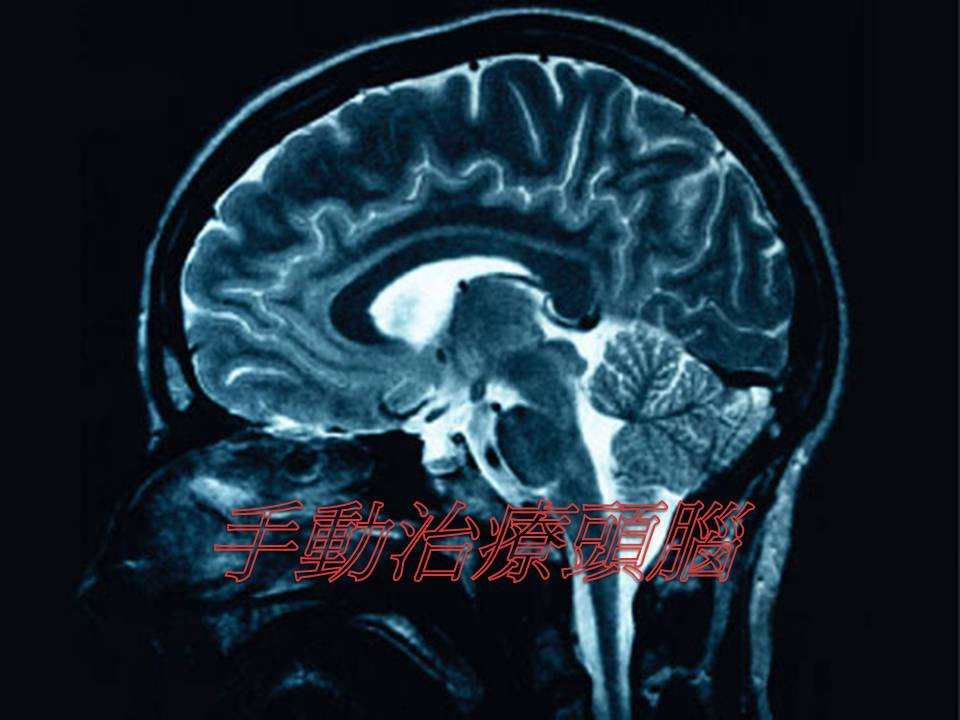

手动治疗头脑